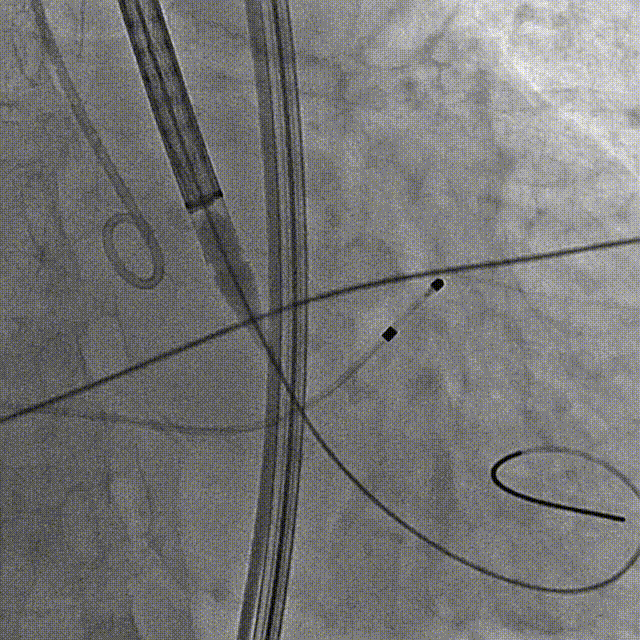

主动脉根部造影

过弓

定位造影